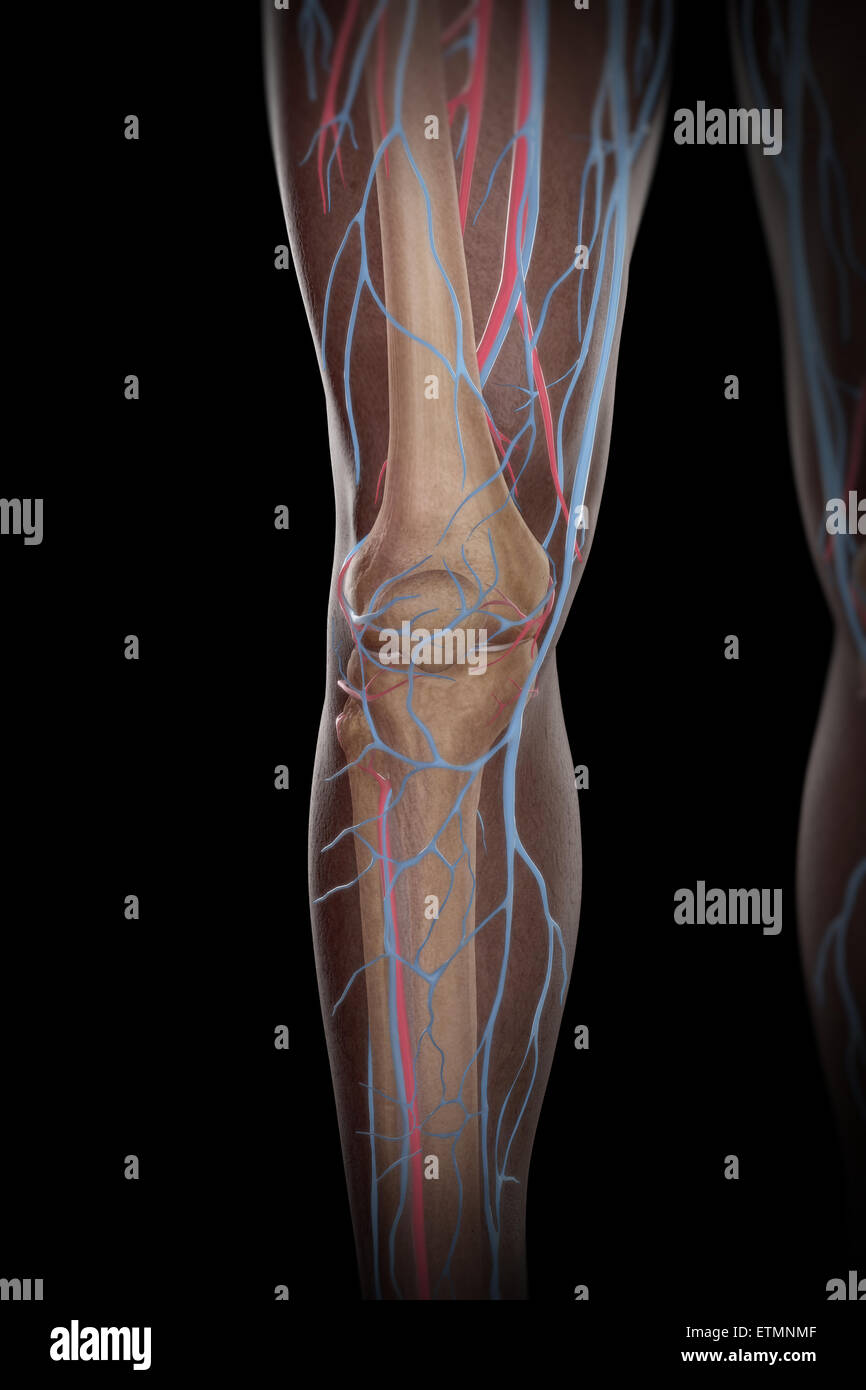

RF2KDED11–Arterielle Versorgung des vorderen und hinteren Beins über die Arteria poplitealis und ihre Zweige

RMETMN27–Darstellung der Blutversorgung und Skelett-Struktur der Unterschenkel, durch die Haut sichtbar.

RMETMNMF–Darstellung der Blutversorgung und Skelettsystem an den Unterschenkeln, durch die Haut sichtbar.

RMETMP9E–Darstellung der Blutversorgung und Skelett-Struktur der Unterschenkel, durch die Haut sichtbar.